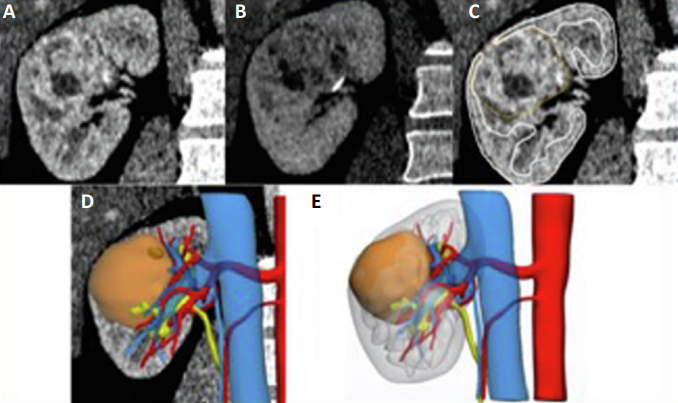

(A,B) 具有对比增强的计算机断层扫描 (CT) 扫描。 (C) 分割阶段以识别不同的解剖结构。 (D) 获得的 3D 模型可以在 CT 图像上重叠。 (E) 3D 虚拟模型可视化。

该3D影像可以上传到任何电子设备,如2D大屏、头戴式显示系统、机器人控制台等,以进行虚拟 3D 可视化,或者可以使用3D 打印机来打印 3D模型。如下图所示: